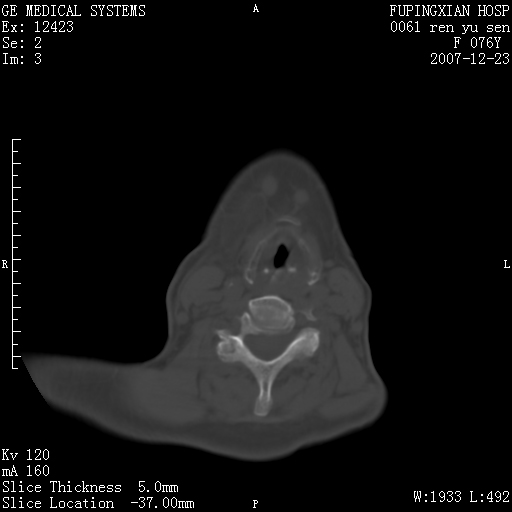

男性 76岁 下颌右侧磨牙区肿物数月, 约2.0*1.5cm大小波及颊舌侧,伴颌下淋巴结肿大。余(-)

右颈部颌下腺前可见一类圆形软组织密度影,密度不均,内见小片坏死区.颌下颈前可见两枚肿大淋巴结影.考虑淋巴结感染可能性大,建议增强扫描..

右侧第四磨牙缺失,局部牙槽骨质破坏,边界欠清晰,同侧颌下及竟不见多发肿大淋巴结显示。考虑肿瘤病变可能性大,感染待排